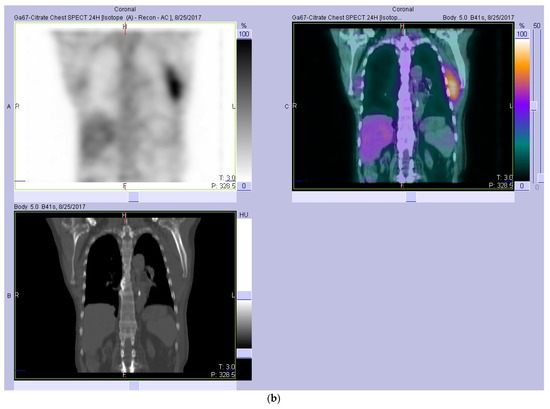

2. Case Report